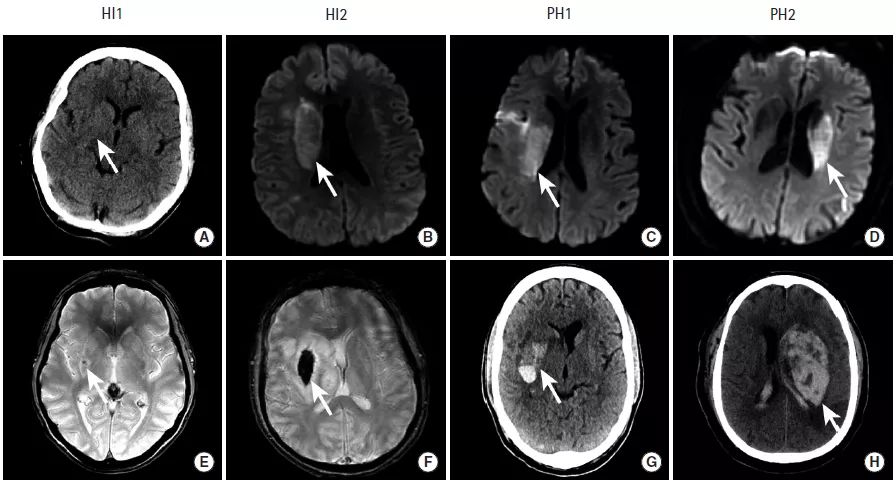

图10

本组图片给出了4例患者的影像学检查,患者在接受血管内治疗完成血运重建后,出现了缺血性脑卒中后的出血性转化,这些患者的出血性转化分别属于4种类型:HI-1型、HI-2型、PH-1型、PH-2型。

HI-1型:沿梗死边缘的小的点状出血

HI-2型:梗死区内片状出血,无占位效应

脑实质出血(Parenchymal Hematoma,PH)

PH-1型:有血肿形成,占位效应轻,小于梗死面积的30%

PH-2型:血肿超过梗死面积的30%,有明显占位效应以及远离梗死区的出血